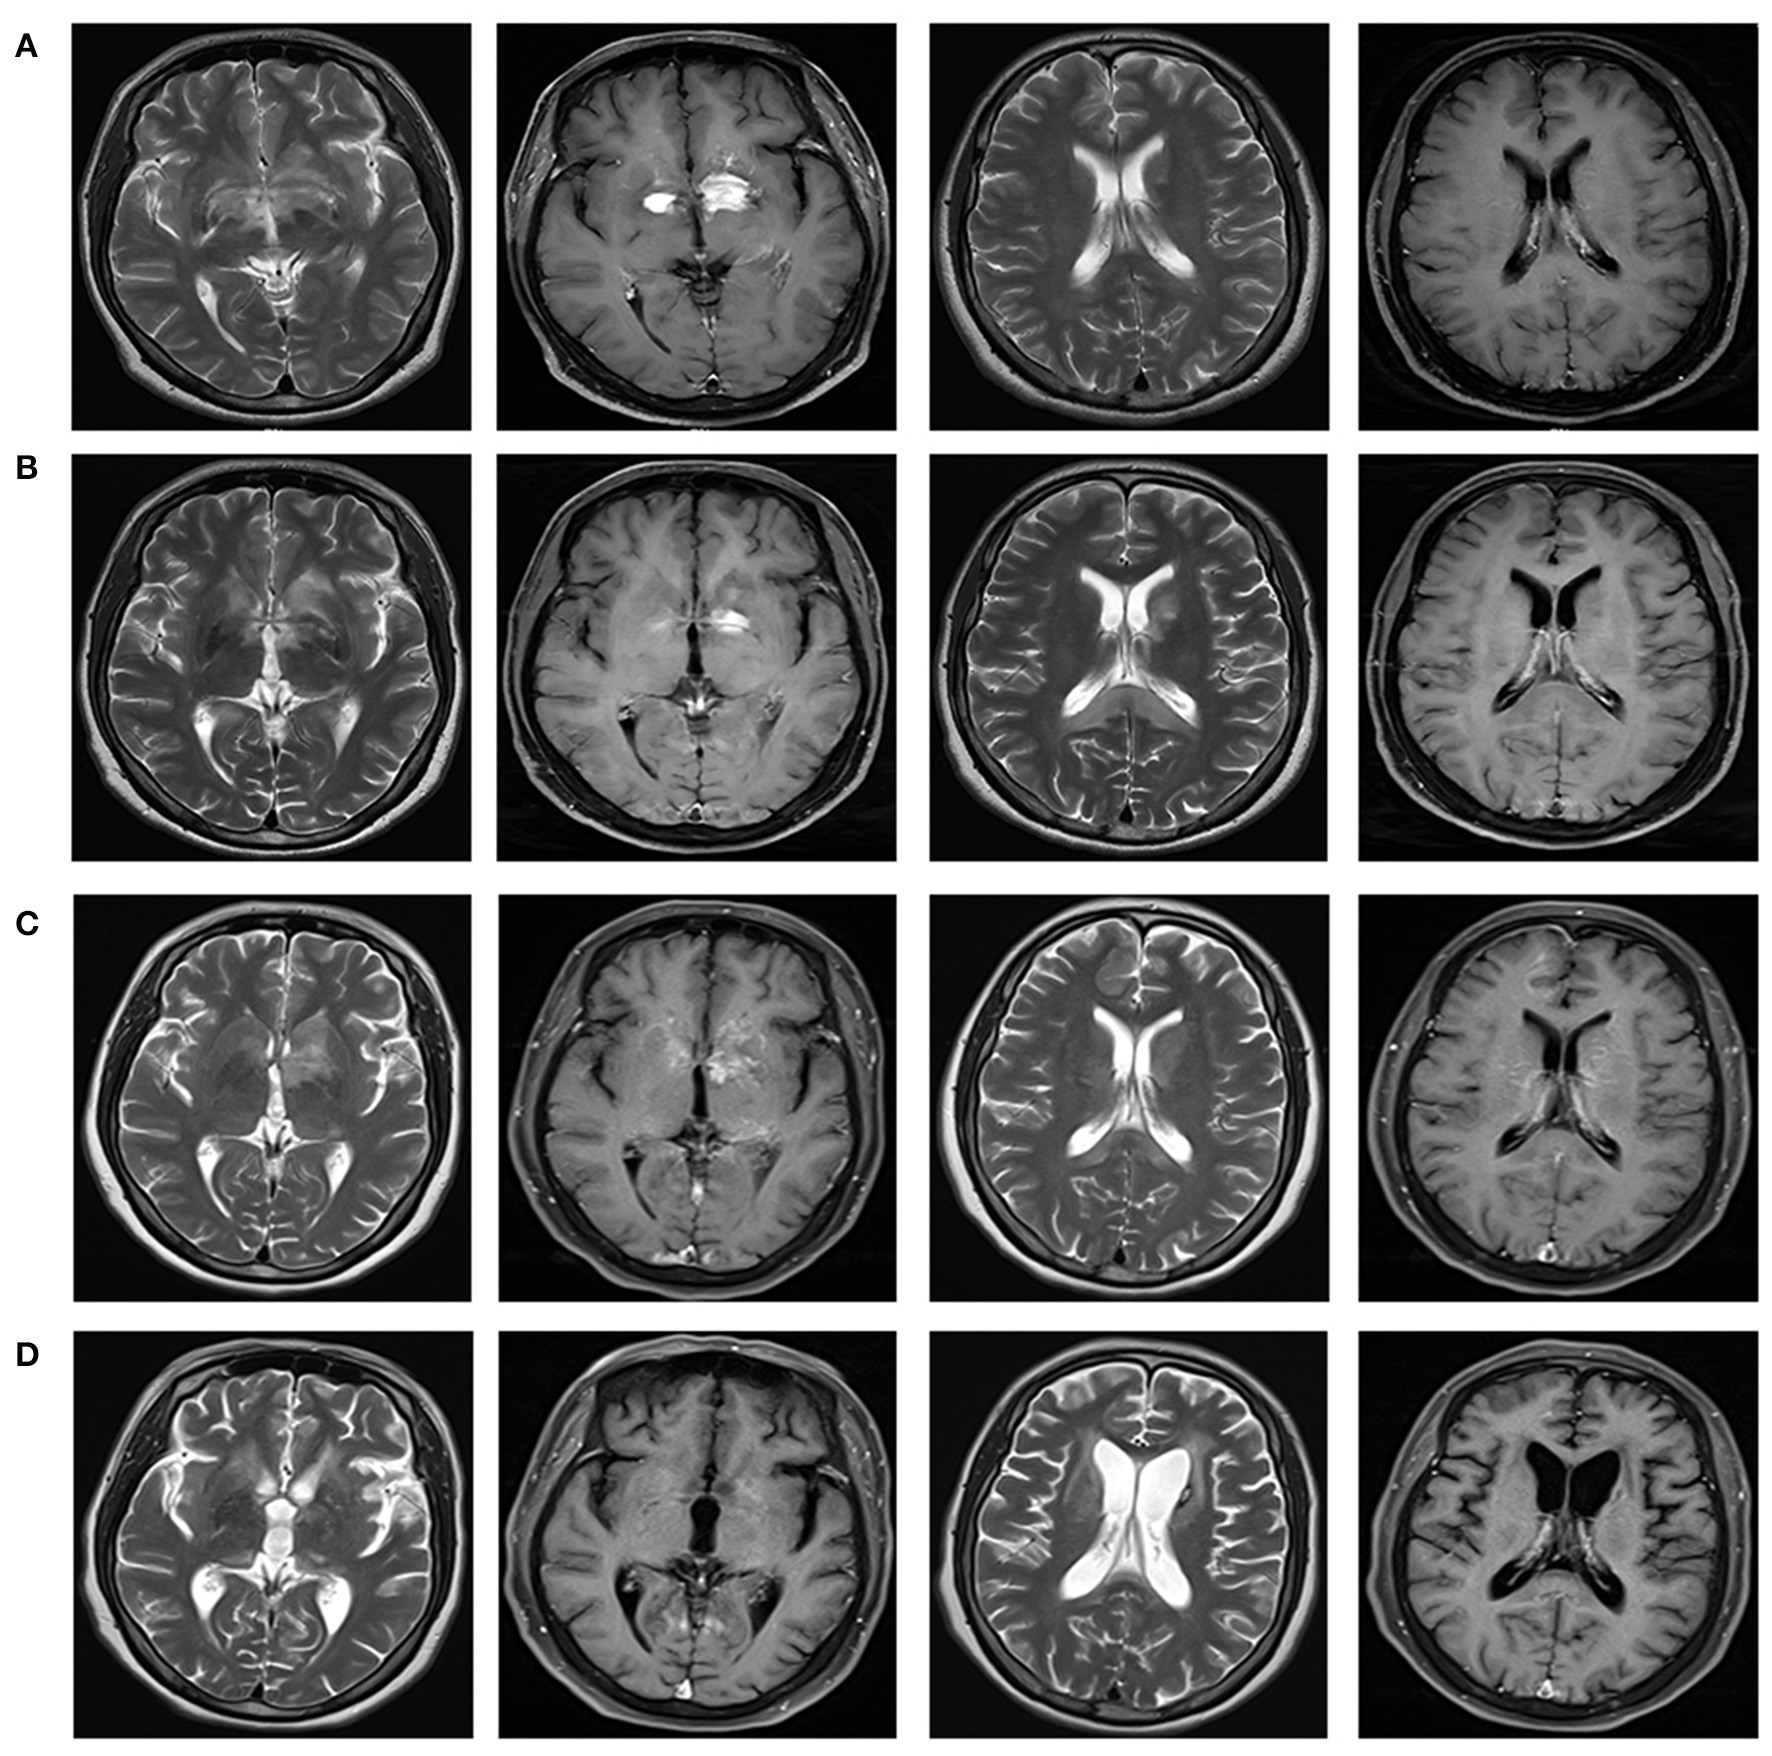

Figure 2

Brain magnetic resonance imaging reflecting the imaging changes of lesions in bilateral basal ganglia and around the third ventricle, and the changes of splenial corpus callosum lesions during the course of disease. Brain MRI with T2-weighted and T1 contrast-enhanced were shown in different columns. (A) In December 2020, multiple abnormal enhancement lesions in bilateral basal ganglia and around the third ventricle were demonstrated. (B) In January 2021, lesions in bilateral basal ganglia and around the third ventricle reduced significantly with less enhancement. A new T2 signal in the splenium of the corpus callosum without enhancement was shown. (C) In March 2021, lesions in bilateral basal ganglia and around the third ventricle were the same as before, with increased enhancement. Attenuated T2 signal abnormality in the splenium of the corpus callosum was observed. (D) In August 2021, lesions in the bilateral basal ganglia and around the third ventricle significantly reduced, with complete resolution of the enhanced lesions. Abnormal signal foci in the splenium of the corpus callosum disappeared.

On December 25, 2020, a 51-year-old Chinese female went to our hospital with chief complaints of somnolence for a month, and memory declination for 10 days. No previous history of infection or vaccination before disease onset was found. Her medical and family history was unremarkable. A weight loss of more than 10 kg was reported in the last month. Pertinent positive finding on physical examination at hospital admission included somnolence. Her cranial nerves, strength, and sensory examinations were normal. Antinuclear and antineutrophil cytoplasmic antibodies, human immunodeficiency virus, hepatitis B virus, hepatitis C virus, JC virus, and syphilis were negative. Chest X-ray, abdominal ultrasonography, and gynecological ultrasonography were normal. Lumbar puncture revealed a slightly elevated white blood cell count (12/mm3) with 83% monocytes and a nearly normal protein level of 0.455 g/l (normal range: 0.15–0.45 g/l). High titers of anti-GFAP IgG antibodies (1:32) were found in CSF but not in serum (Figure 1). No malignant cells were found in the CSF. Tests of other autoantibodies in CSF and serum, including MOG-IgG, MBP-IgG, AQP4-IgG, NMDAR-IgG, AMPA-IgG, LGI1-IgG, CASPR2-IgG, and GABABR-IgG were negative. Blood neoplastic and paraneoplastic markers were negative. Electroencephalogram indicated mild abnormality. FDG-PET scan suggested autoimmune or infectious lesions, however neoplasia cannot be excluded. There were patchy and nodular areas with increased glucose metabolism in bilateral basal ganglia and periventricular area. Magnetic resonant imaging (MRI) of brain (Figure 2A) showed multiple abnormal enhancement lesions in bilateral basal ganglia and around the third ventricle. Based on clinical data and CSF analysis, a diagnosis of GFAP astrocytopathy was established. The patient was treated with intravenous methylprednisone (1,000 mg for 3 days) followed by a 50% reduction of the dose after 3–5 days, and subsequently oral prednisone tablets (60 mg/day), which was then tapered (reduced 5 mg/day every 2 weeks). A repeated brain MRI (Figure 2B) scan showed a significant reduction in the former lesion size and a new T2 signal in the splenium of the corpus callosum without contrast enhancement. After discharge, the patient took prednisone to inhibit immunity. Her drowsiness and short-term memory has significantly improved. One month after discharge, the patient went to the outpatient clinic of our hospital for follow-up. A repeat CSF analysis was unremarkable. The GFAP antibody in CSF and serum was negative. She was admitted again for cognitive impairment and slow response when the dose of prednisone reduced to 45 mg. Positive physical examinations included somnolence, near memory loss and decreased computational ability. A rechecked lumbar puncture revealed 0 WBC/μl, glucose of 4.42 mmol/L, and normal protein level (451 mg/l). Serological tests for infectious, autoimmune, and neoplastic parameters were all normal. The GFAP antibody in CSF and serum was negative either. The brain MRI scan (Figure 2C) showed attenuated T2 signal abnormality in the splenium of the corpus callosum, but lesions in bilateral basal ganglia and around the third ventricle were the same as before, with increased enhancement, and new lesions in the right frontal lobe. PET-CT demonstrated enhanced glucose metabolism in the bilateral basal ganglia and periventricular area, with lesion size larger than before and there was new nodular increase of glucose metabolism under the right frontal cortex. Considering the poor response to steroid therapy, coexistence of malignancy was suspected and a stereotactic brain biopsy was adopted.

The patient was transferred to the department of oncology for further treatment. She received a chemotherapy regimen of rituximab plus methotrexate every 21 days. After three courses of chemotherapy, her drowsiness and cognitive impairment significantly improved. Follow-up brain MRI showed resolution of abnormal signal foci in the splenium of the corpus callosum, and lesions in the bilateral basal ganglia and around the third ventricle significantly reduced with complete resolution of the enhancing lesions (Figure 2D). At present, she can complete simple daily activities, such as eating, combing her hair, and dressing.